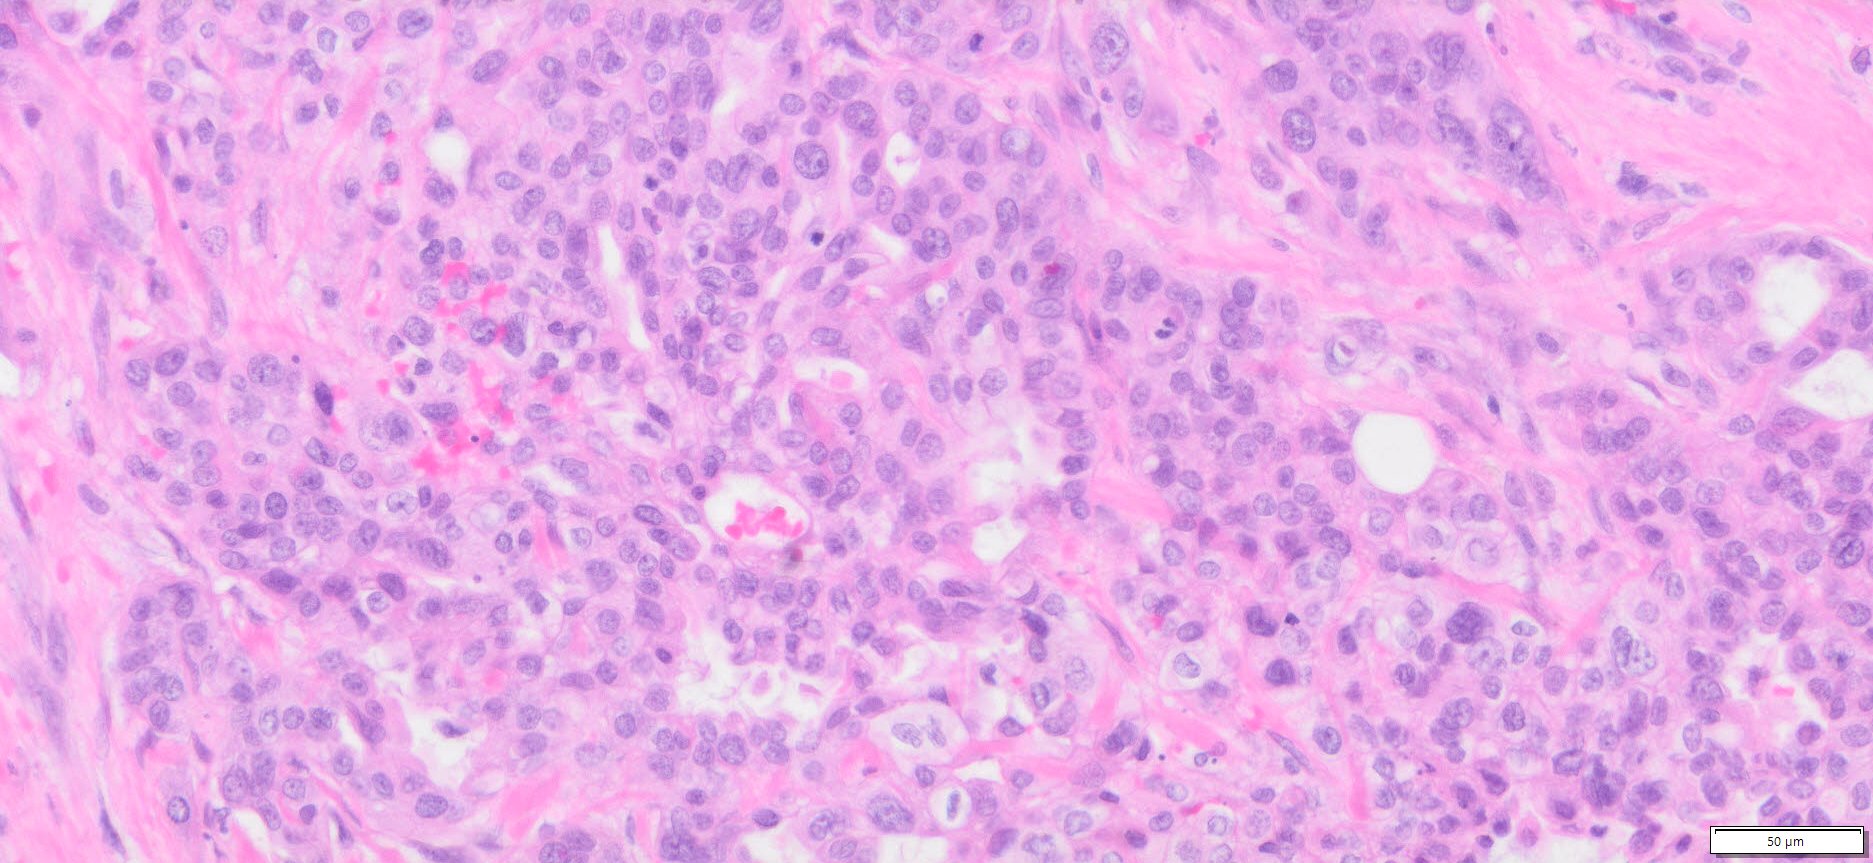

Description

| Tissue | Pathology Diagnosis | Gender/ Age (year) | %Tumor Area | Tumor Grade | TMN/Stage | IHC data |

| Pelvic mass | Human bile duct adenocarcinoma | Female/66 | 30% | II | T3N1M0 | MLH1,2,and6, PMS2 show intact nuclear expression |